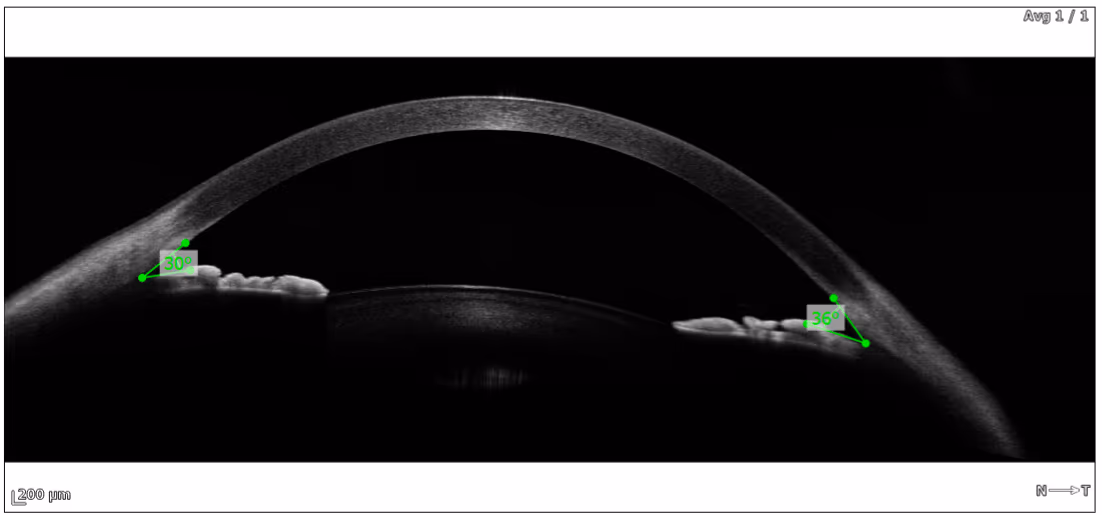

A topografia de coerência óptica (OCT ou TCO) é um moderníssimo exame que usa uma luz especial para estudar a CÓRNEA do olho humano.

Nosso novo equipamento de alta tecnologia, importado da Polônia, faz imagens de altíssima resolução da córnea do olho humano.

A topografia de córnea é um exame clássico que avalia a superfície anterior da córnea — essencial para que a luz tenha foco dentro do olho. Nosso equipamento (REVO 60 da Optopol) vai além e avalia também a superfície posterior da córnea, permitindo o diagnóstico de casos iniciais de ceratocone, avaliação de cirurgia de catarata e avaliação de cirurgia refrativa.

A topografia de coerência óptica (OCT ou TCO) é um moderníssimo exame que usa luz especial para estudar a córnea do olho humano. Nosso equipamento, importado da Polônia, faz imagens de altíssima resolução da córnea humana.